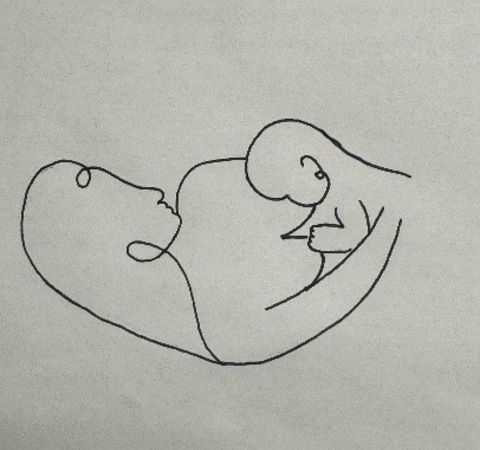

Stillen besteht nicht nur aus Nahrungsaufnahme. Es bedeutet gleichzeitig Kuscheln, Schmusen und intensiven Hautkontakt, den gerade ein Frühgeborenes oder krankes Neugeborenes dringend braucht.

Frühgeborene Kinder liegen oft in einem Inkubator. Durch das Känguruhen wird es Ihnen als Eltern ermöglicht in engen Hautkontakt, im besten Fall nackte Babyhaut auf nackte Brust des Elternteils, mit Ihrem Kind zu kommen und ihm so Nähe und Geborgenheit zu vermitteln. Dafür sollten Sie sich täglich Zeit nehmen.